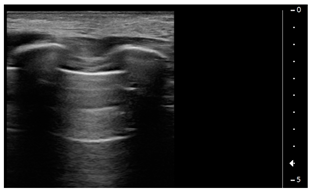

- Normal lung sliding, regular pleural line, and A lines

![]() | PATTERN 1 Normal lung sliding, regular pleural line andA lines |